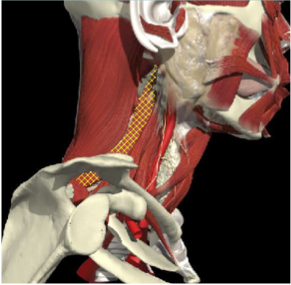

ACCURACY OF LOCALIZATION - SCALENES

ACCURACY OF LOCALIZATION LEVATOR SCAPULAE

LOCALIZATION OF MUSCLES IN DEEPER LAYERS

Layer 1

Layer 2

Layer 3

Splenius Capitis

Semispinalis Capitis

Longissimus Capitus

Semispinalis Cervicis

ACCURACY OF LOCALIZATION – DEEPER LAYERS